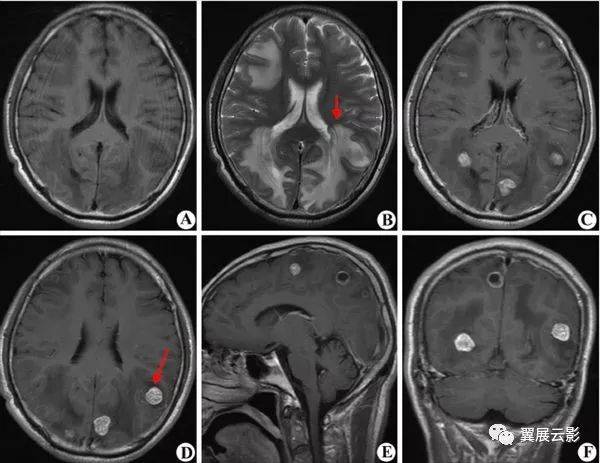

(图1:起病时的脑mri;flair[a],dwi[b]和t1增强[c]提示脑脓肿)(图2:4月